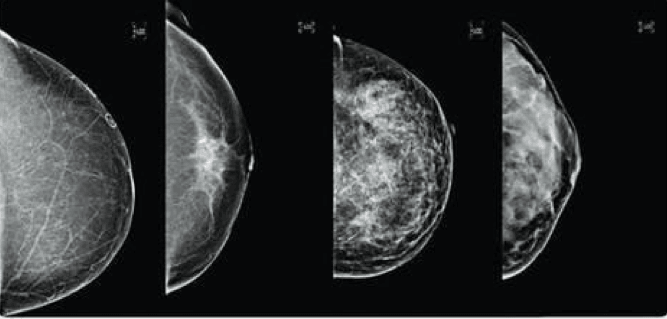

Dr Saini: A mammogram is an x-ray. It takes two images of each breast and it requires a squeezing of the breasts between two plates so that the breast tissue can be spread out and a radiologist can identify changes including breast cancer. Mammograms look through the breast tissue.

“I’m a visual person and radiology is all about interpreting subtle changes in a woman’s images. I fell in love with it because I had a wonderful mentor who could tell a story about a woman by just examining her chest x-ray,” she says.

“There’s an art to interpreting mammography and holistically understanding a woman’s body is key.”